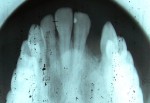

Alveolar Cleft (Defect in the Upper Jaw) Repaired with a Hip Bone Graft

Before